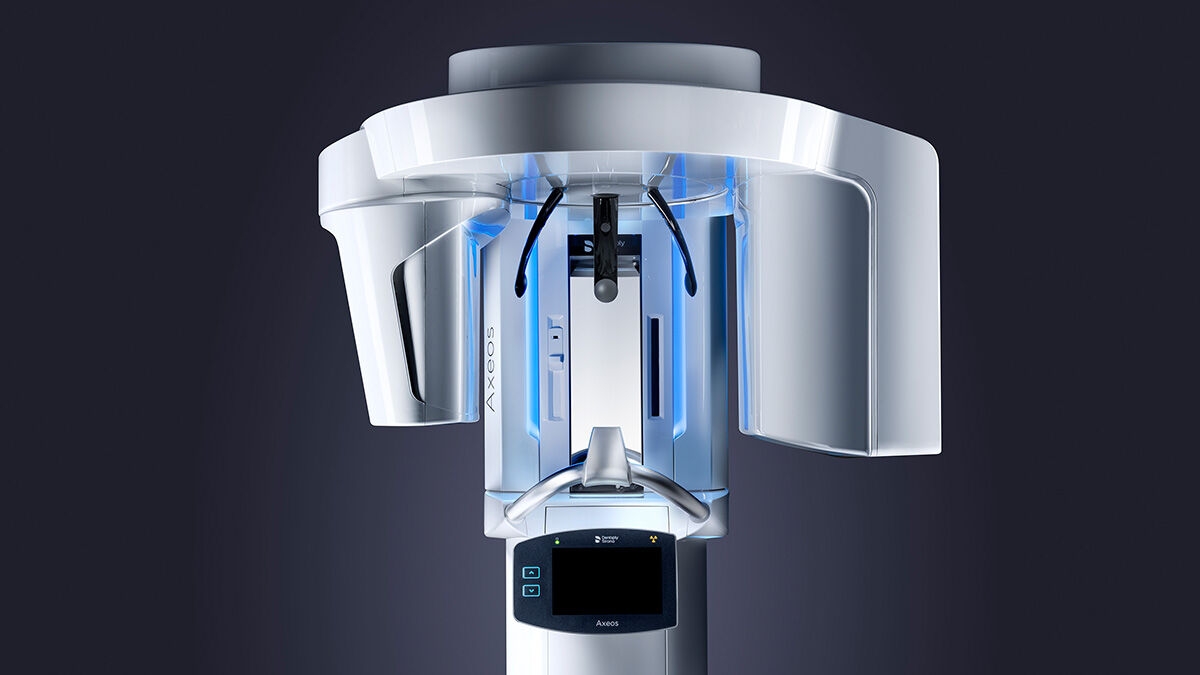

Patient Positioning & Image Assistant

We developed a 10-point concept for easy patient positioning and X-ray imaging. Our concept is primarily about two things: high image quality and comfort for the patient and the assistant. This concept supports and provides the tools needed to ensure high-quality images for treatment analysis and focuses on ergonomics and comfort for the patient and assistant. The patented bite block technology, for example, automatically establishes the correct inclination of the patient's head, positioning the patient in the occlusal plane, partnering with the 3 point head fixation and firm handles to ensure stable positioning-limiting unnecessary correction scans.